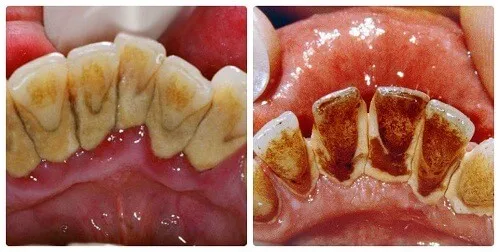

Cao răng là những mảng bám bám chặt vững chắc vào bề mặt răng theo thời gian. Tuy nhiên, nhiều người vẫn còn chủ quan việc chăm